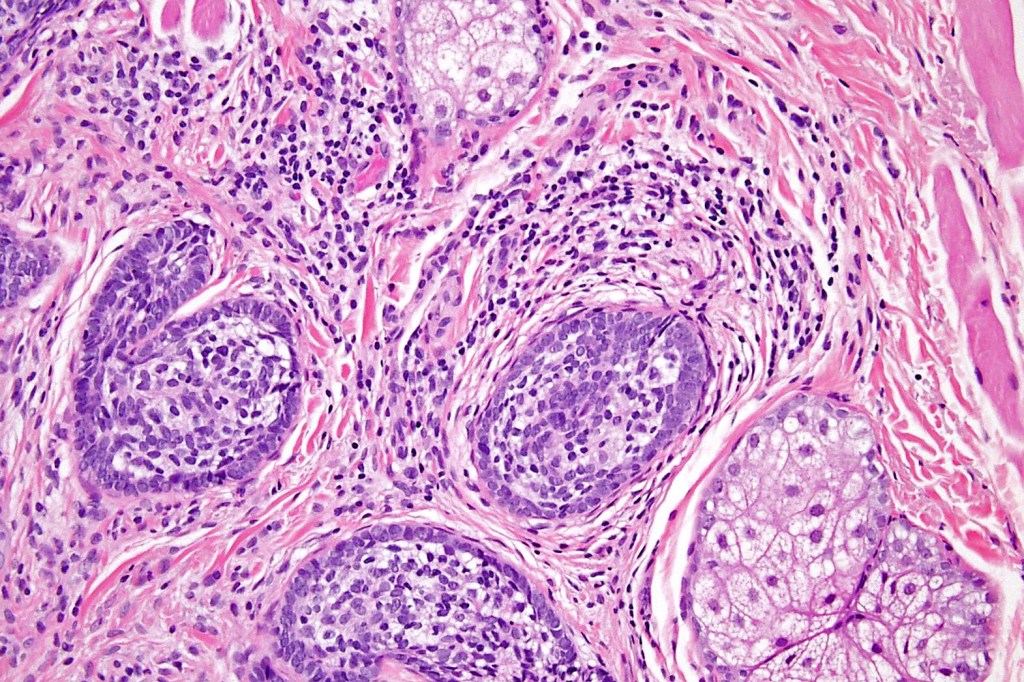

•Irregular lobules of epithelial cells embedded in a dense fibrous stroma

•Peripheral rim of darkly staining basaloid cells surrounding larger pale staining cells with vesicular nuclei with often prominent eosinophilic nucleoli

•Admixed lymphocytes (an obligatory feature)

•Germinal centers sometimes present

•+/- focal sebaceous differentiation (rare)

•+/- focal ductal differentiation (rare)